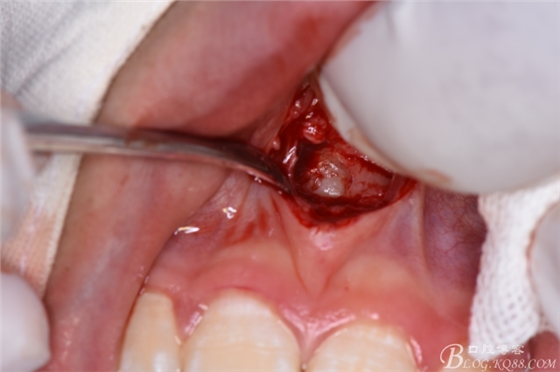

圖11.暴露出整個(gè)多生牙牙冠

圖12.將暴露多生牙牙冠分成牙根河牙冠兩部分